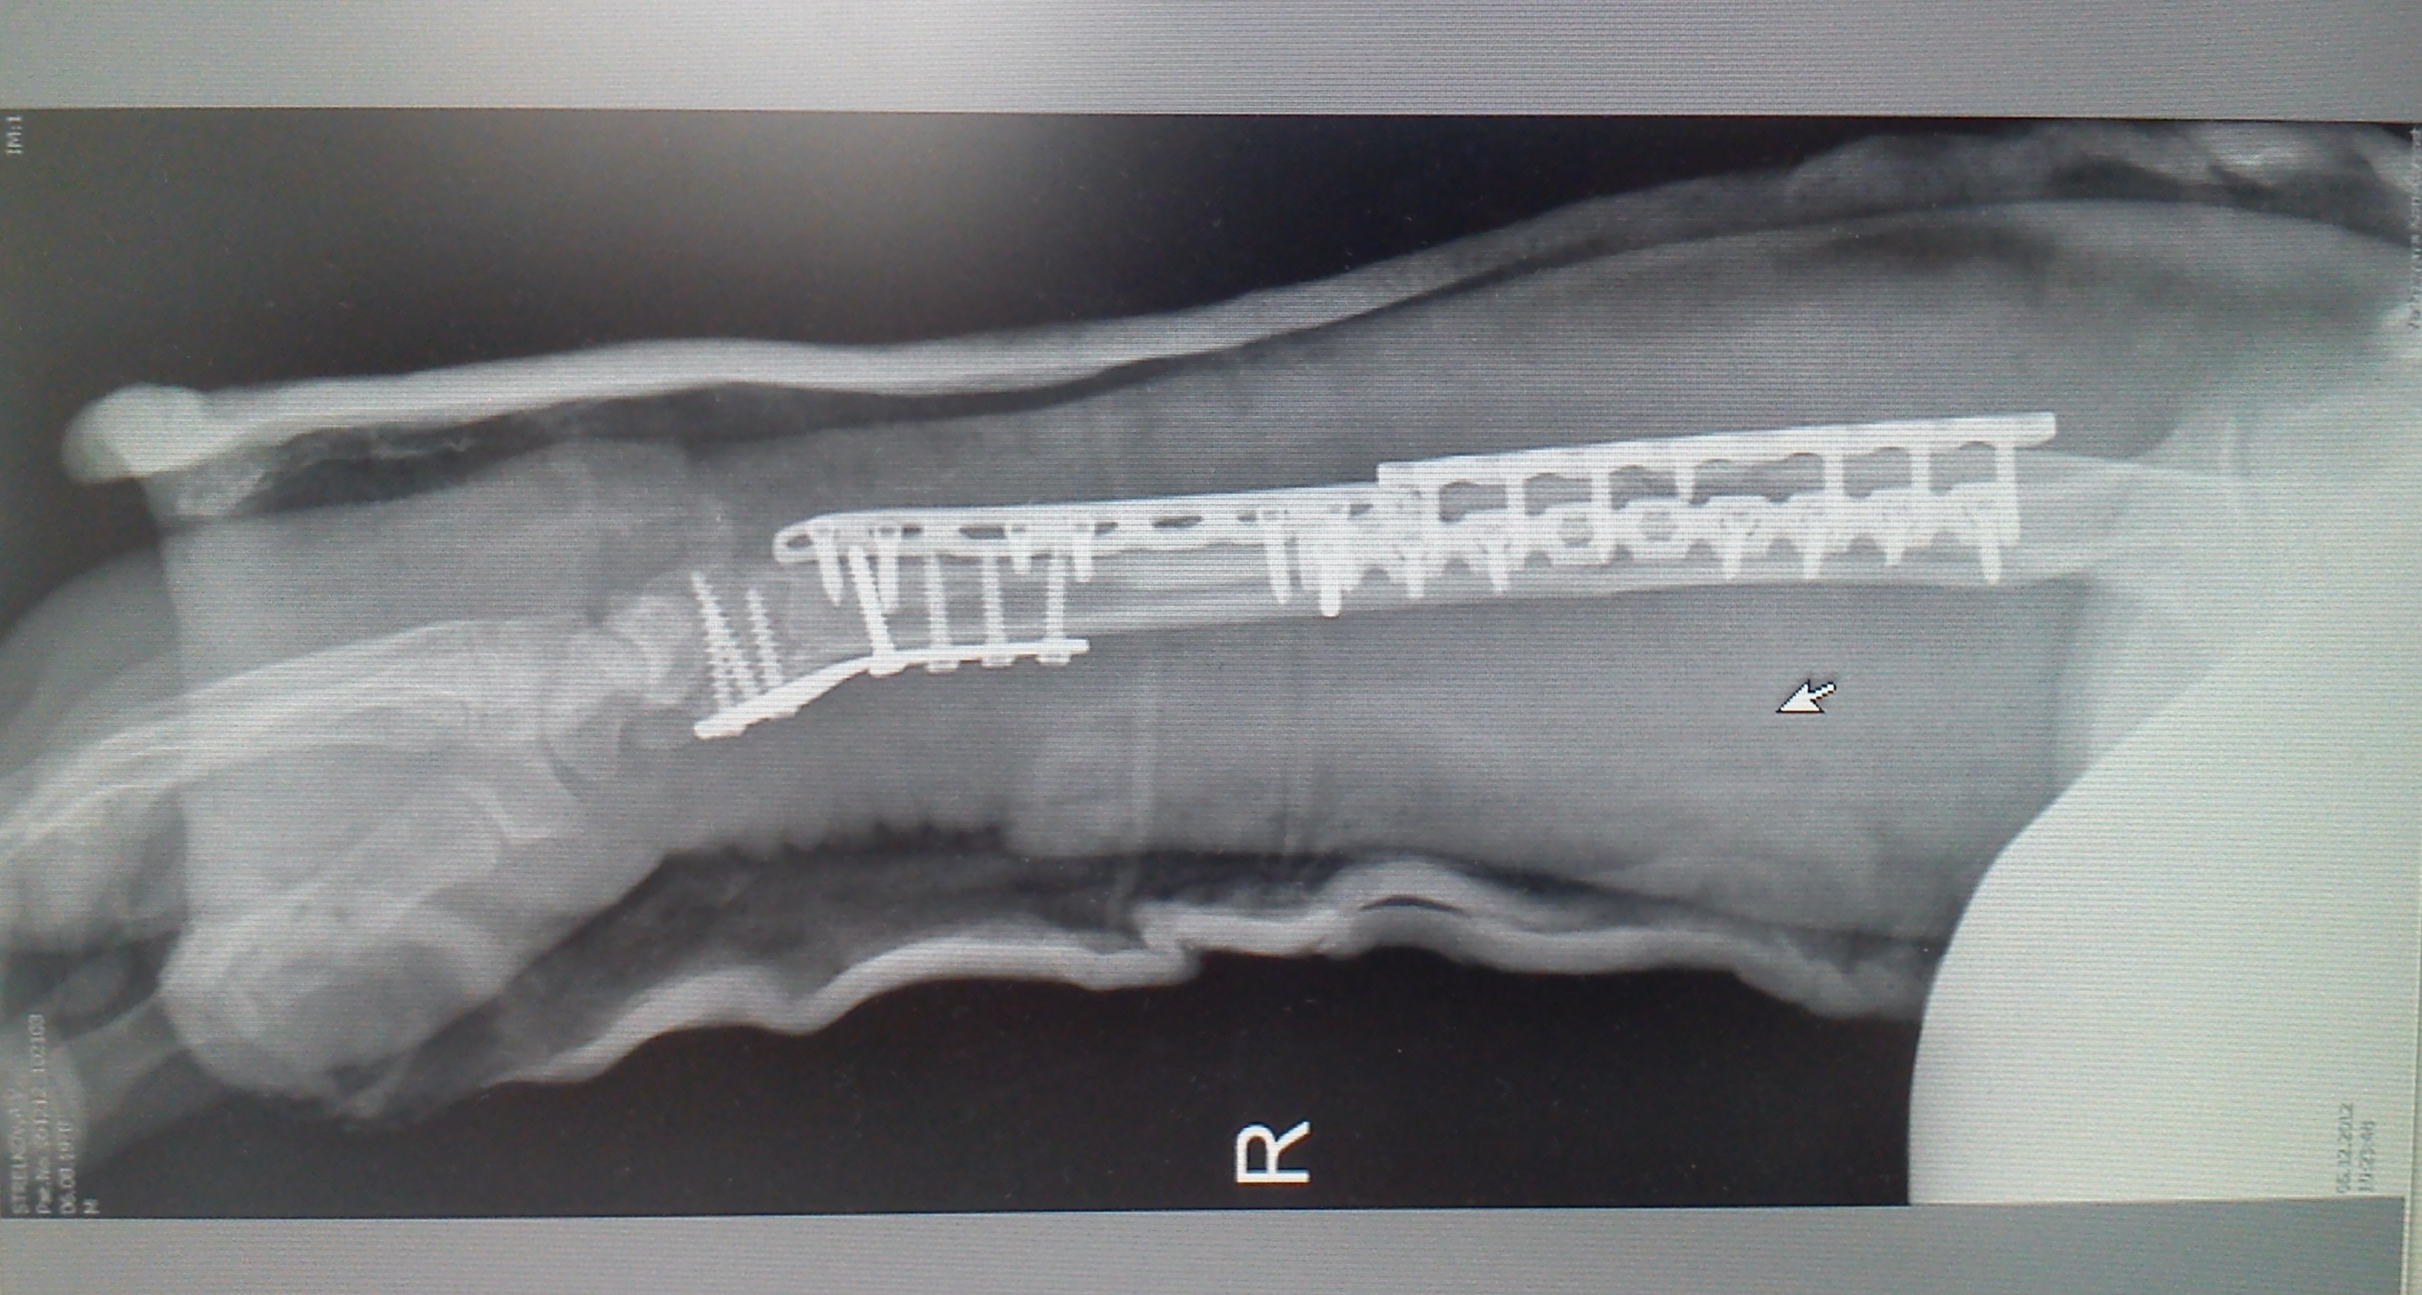

Медицинские снимки: Пластина в левом предплечье

Раздел: Альбом идей